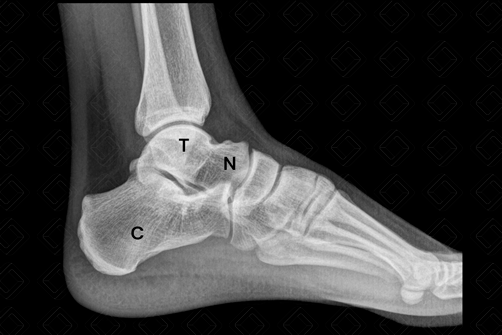

Texto alternativo para a imagem Radiografia do calcâneo - perfil. Créditos: Athena Hub/Medical Harbour

Legenda das siglas: C = calcâneo; N = navicular; [cms-watermark] T = tálus.